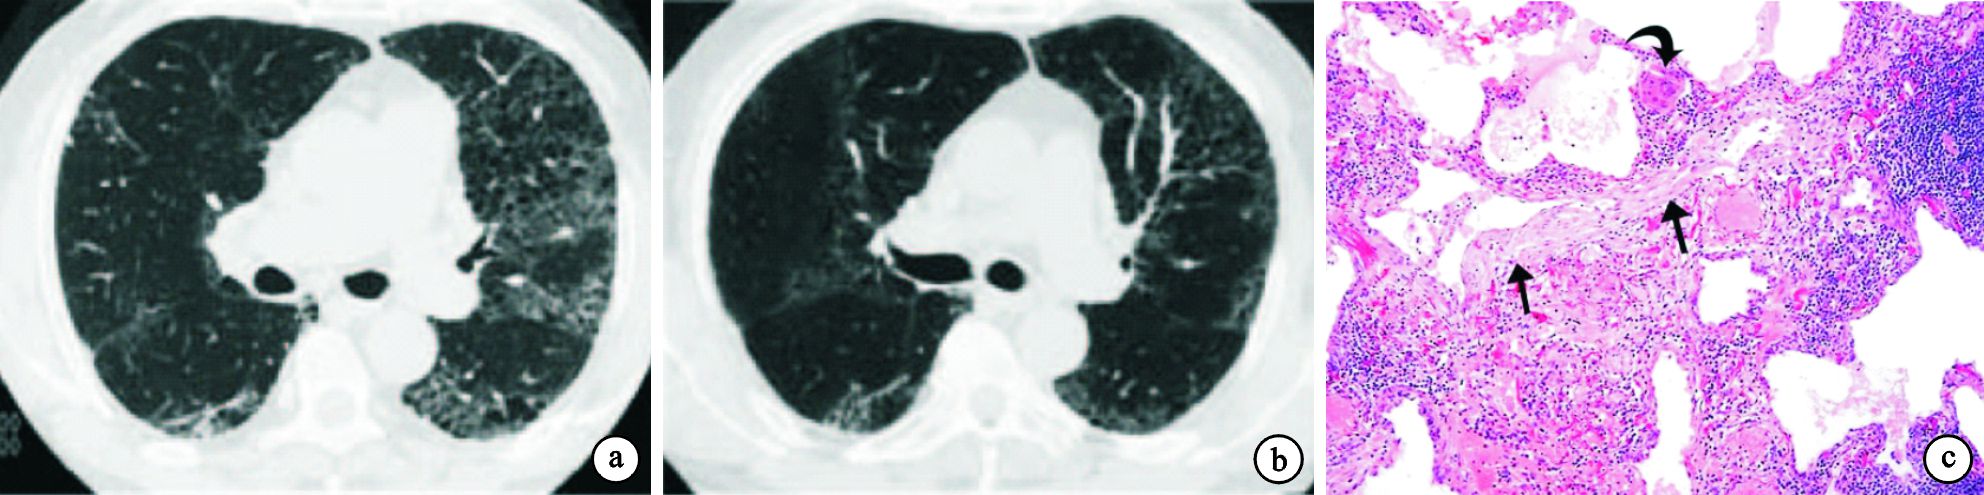

24例患者的主要胸部HRCT特征總結見表 1。17例(70.8%)雙肺彌漫分布磨玻璃影,多呈斑片或片狀;15例(62.5%)雙肺彌漫分布細支氣管或小葉中心結節,邊緣模糊;10例(41.7%)氣體陷閉或馬賽克征;5例(20.8%)有網格影或伴蜂窩肺。上述改變常重疊存在,磨玻璃影伴馬賽克征10例,小葉中心結節影伴馬賽克征9例,磨玻璃影、小葉中心結節伴馬賽克征7例,彌漫磨玻璃影伴實變影4例,網格影或伴蜂窩肺伴磨玻璃影2例。2例急性患者分別表現為彌漫磨玻璃影伴實變影(圖 1a、圖 2a),脫離暴露因素并給予甲基潑尼松龍靜滴,后改為潑尼松治療后,3周內病變明顯吸收(圖 1b、圖 2b)。17例亞急性患者中14例(82.4%)為彌漫分布的小葉中心結節(圖 3a、圖 4a),3例(76.5%)為磨玻璃影,8例(47.1%)為馬賽克征,8例(47.1%)為彌漫分布的斑片磨玻璃影伴馬賽克征。脫離暴露因素并給予潑尼松治療后病變均明顯吸收(圖 3b、圖 4b)。5例慢性患者均表現為網格影或伴蜂窩肺(圖 5a),其中2例伴斑片磨玻璃影,1例伴馬賽克征,1例伴小葉中心結節。

急性期2例行TBLB檢查,病理為肺泡壁和細支氣管壁水腫,以淋巴細胞性肺泡和間質炎癥為主,而嗜酸粒細胞浸潤較少。肺泡腔內有蛋白滲出及炎癥細胞(圖 1c、圖 2c)。亞急性期17例均行TBLB病理檢查,其中11例間質中見非干酪性壞死肉芽腫(圖 3c),其對應的HRCT表現為典型的小葉中心結節,另6例見單核細胞浸潤所致的細支氣管炎(圖 4c)。慢性期5例中有1例開胸肺活檢,病理見纖維化及成纖維細胞灶(圖 5c),其對應的HRCT表現為網格影伴蜂窩肺或牽拉性支氣管擴張(圖 5a)。1例因急性加重死亡,其余3例行BALF檢查。22例(2例急性,17例亞急性,3例慢性)BALF檢查提示肺泡淋巴細胞滲出為主的炎癥,巨噬細胞(31.5±18.3)%,淋巴細胞(36.4±19.7)%,中性粒細胞(22.4±18.5)%,嗜酸粒細胞中位數為2.3%(0.5%~4.5%)。CD4/CD8 T淋巴細胞比值中位數為0.96(0.48~1.61)。